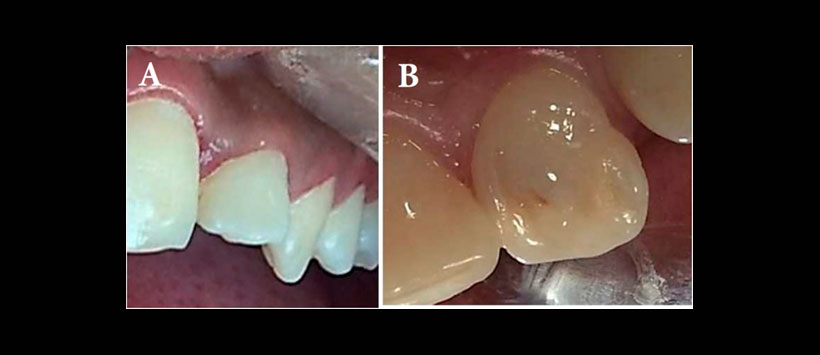

El presente caso es de una paciente de sexo femenino de 12 años de edad que fue derivada al departamento de manifestando dolor en el incisivo lateral superior izquierdo El examen extraoral inicial no reveló hinchazón en el lado izquierdo del maxilar. Había una fosa palatina en el diente 2.2 (Figura 1) y el diente era sensible a la palpación y la percusión. Una radiografía periapical inicial y CBCT mostraron la presencia de DI tipo 2 (Oehler) en el diente, asociado a radiolucides periapical y reabsorción de raíz interna (Figura 2). Dado que la morfología de la invaginación no era clara en la radiografía periapical, se usó CBCT para un diagnóstico y protocolo de tratamiento óptimos. El escaneo CBCT reveló dos canales separados. El canal invaginado estaba casi en el centro de la raíz, pero el otro canal estaba localizado mesiolingualmente. También se observó la reabsorción de la raíz asociada con el canal invaginado (Figura 3). El paciente fue tratado en dos sesiones. En la primera visita, se aplicó anestesia local con lidocaína al 2% que contenía epinefrina y se aisló el diente con dique de goma. La cavidad de acceso endodóntico fue preparada. Luego, la longitud de trabajo se determinó mediante radiografía periapical y el localizador de ápices. El canal invaginado se encontró fácilmente y el segundo canal se encontró usando CBCT.